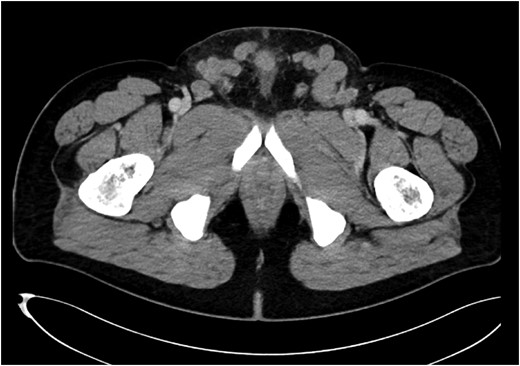

For verification of the clinical diagnosis a Doppler ultrasound was performed by an experienced ultrasound examiner. In the ultrasound a hernia with prolapsed intestine was diagnosed due to a tubular, hypoechoic, non-compressible, inguinal mass with no flow evident on color Doppler imaging (Fig. 2). However, it was unclear whether the hernia was caused by a bilateral or unilateral gap. Only for surgery planning purposes we decided to perform a CT scan to identify the side of the gap and classify the kind of hernia (direct/indirect). Surprisingly the CT scan showed large venous collaterals between left and right Vena femoralis and a illio-femoral thrombosis on the left side. No inguinal or any other hernia of the suprapubic and inguinal regions were found (Fig. 3). The venous collaterals showed extensive signs of inflammation—concordant with the diagnosis of a local suprapubic thrombophlebitis. After the CT scan the patient was re-evaluated by Doppler ultrasound. Knowing the CT scan results and by readjustment of Doppler settings that diagnosis was confirmed.

A CT-abdomen revealed suprapubic crossover collaterals due to ilio-femoral vein occlusion secondary to DVT.